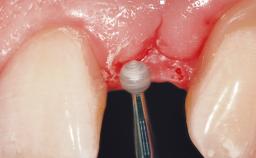

A 30-year-old female patient was referred to the office for the treatment of tooth 11. Her chief concern at the initial visit was to inquire, “Why is my tooth pink?” Upon clinical examination, it was determined that tooth 11 had a previous history of trauma and that the clinical crown had become noticeably pink in color as a result of internal resorption. This diagnosis was confirmed radiographically, indicating a large radiolucency involving the central and distal portions of the clinical crown. It was determined that restoration of this tooth was not possible, and that extraction was indicated. The presence of a mid-line diastema, which the patient wanted to reproduce, directed the treatment plan for tooth replacement utilizing a dental implant.